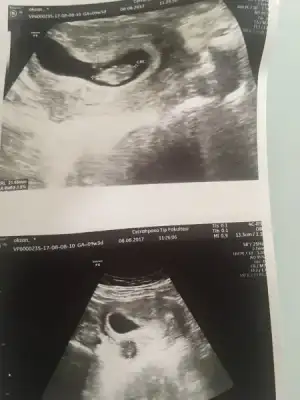

Arkadaşlar 9 haftalık ultrason görüntümüz buna göre yorum yapan arkadaşlar vardı ben anlayamadım bakarmısınız rica etsem

Eklentiler

• image.webp

image.webp

15,7 KB · Görüntüleme: 81